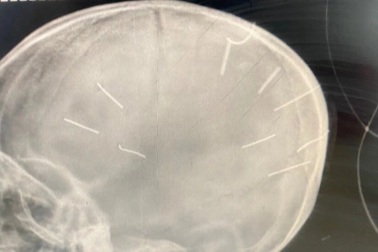

Bé 3 tuổi bị cắm đinh vào đầu: Phụ huynh căm phẫn về hành động man rợ nàySự việc em bé 3 tuổi bị nhân tình của mẹ cắm đinh vào đầu khiến dư luận phẫn nộ, tức giận... nhiều phụ huynh có con nhỏ đã khóc vì sự quá man rợ và tàn nhẫn này.